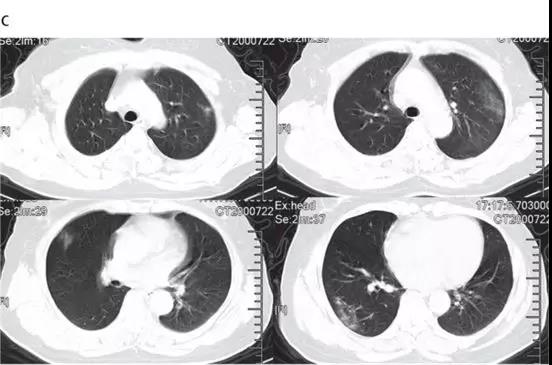

隨后的胸部CT顯示雙側毛玻璃樣混濁,而實變消除(見下圖)。